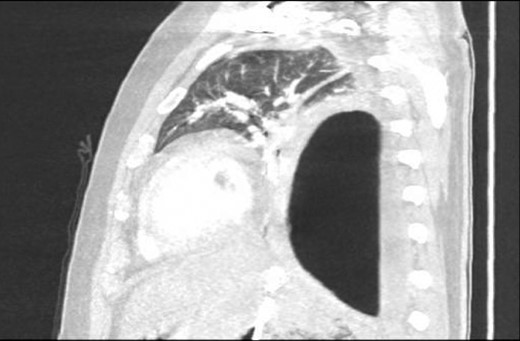

Chest X-ray in ICU following drainage showed what was thought to be Pneumomediastinum (Figs 1 and 2), and given this concern he was referred to the Cardiothoracic service. Subsequent CT suggested a large loculated hydro-pneumothorax, which in retrospect represented the drained Pseudocyst communicating through the diaphragm (Figs 3 and 4).

Area of communication between the drained Pseudocyst and the Left Pleura. Space noted with arrow.

An Intercostal drain was inserted under CT-guidance aiming to decompress the pleural space. Amylase level in the pleural drainage was 880 U/l, Lipase 472 U/l. There was significant reduction of the Hydropneumothorax (Fig. 5). Given his young age, potential for loss of lung volume and infection he proceeded to decortication.